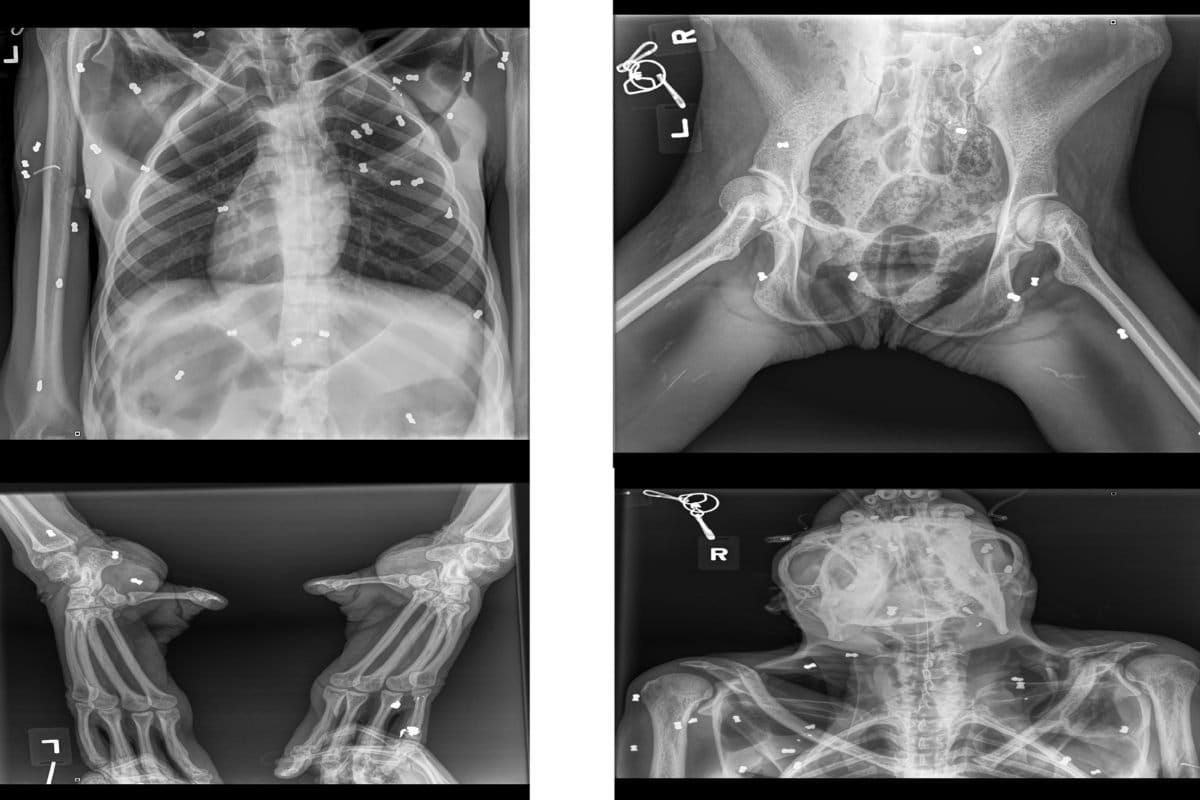

“Hasil x-ray, ditemukan ada sebanyak 74 butir peluru yang tersebar di seluruh badan,” ungkap Kepala BKSDA Aceh Sapto Aji Prabowo, dalam penjelasannya.

Sebutnya, kondisi Hope amat parah saat dievakusi. Pendarahan terjadi di mata kiri bagian kornea dan pupil akibat tiga peluru. Luka lebam di seluruh tubuh, dijumpai di kedua tangan dan ada luka sayatan terbuka di beberapa bagian tubuh.

“Rinciannya, tangan kanan lebar luka 10 cm, tangan kiri luka di bagian jari-jari dengan lebar 2-3 cm. Kaki kanan luka terbuka di bagian paha atas dengan lebar luka 10 cm. Luka terlihat seperti luka sayatan benda tajam, telapak kaki kanan luka terbuka, yang mengakibatkan kerusakan di bagian tendon. Lebar luka 5 cm namun cukup dalam,” ungkap Sapto.

Kaki kiri orangutan itu juga terluka selebar 4 cm dengan kedalaman 1 cm di daerah ruas jari telunjuk. Luka juga dijumpai di bahu kiri dengan lebar luka 1 cm yang cukup dalam, lebih dari 10 cm dan mengenai tulang.